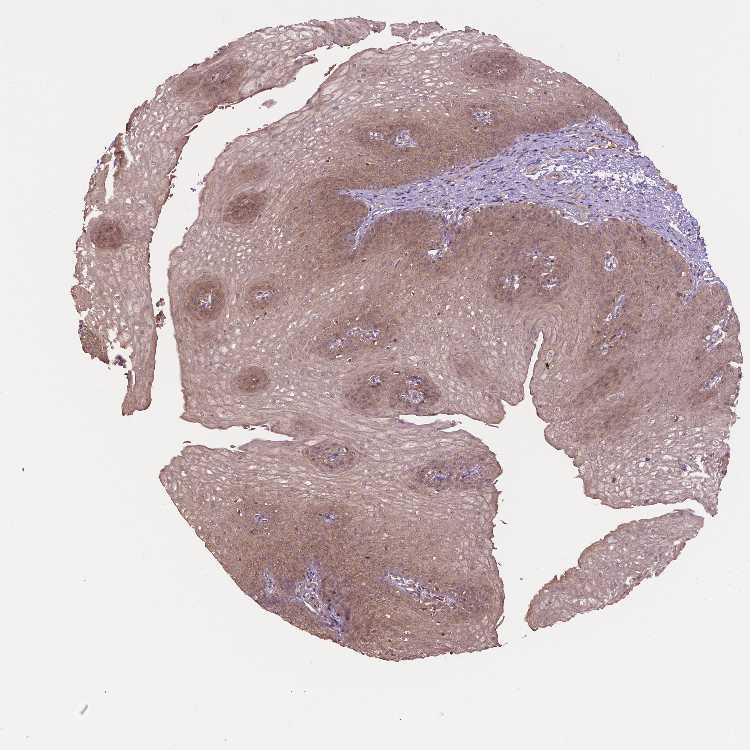

ESOPHAGUS - Antibody stainingi

Antibody staining in the annotated cell types in the current human tissue is reported as not detected, low, medium, or high, based on conventional immunohistochemistry profiling in selected tissues. This score is based on the combination of the staining intensity and fraction of stained cells.

Each image is clickable and will lead to virtual microscopy that enables deeper exploration of all samples and also displays staining intensity scores, fraction scores and subcellular localization as well as patient and tissue information for each sample.

Antibody HPA068473

Squamous epithelial cells Medium